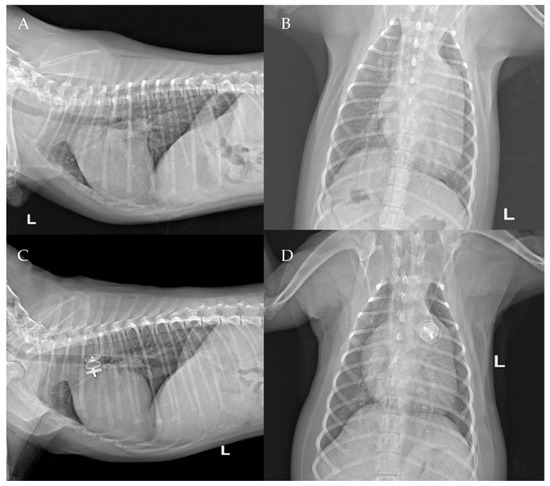

The thoracic radiographs performed before and just after the procedure showed a reduction in the cardiac silhouette as well as significant reduction of the over-circulation vascular pattern for all dogs (Figure 8, Figure 9, Figure 10, Figure 11 and Figure 12).

Figure 8. Pre-procedure (A,B) and post-procedure (C,D) left lateral and dorso-ventral thoracic radiographs of Case 1. L: left; R: right.